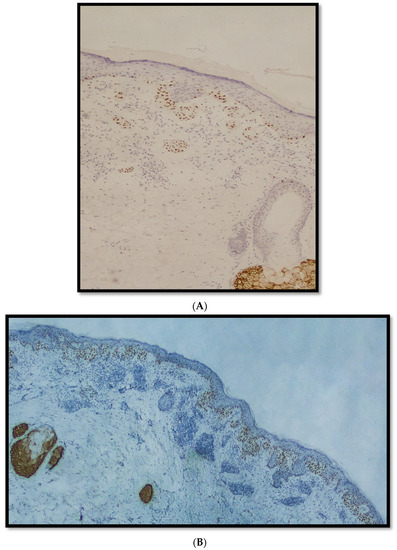

- Cazzato, G.; Mangialardi, K.; Falcicchio, G.; Colagrande, A.; Ingravallo, G.; Arezzo, F.; Giliberti, G.; Trilli, I.; Loizzi, V.; Lettini, T.; et al. Preferentially Expressed Antigen in Melanoma (PRAME) and Human Malignant Melanoma: A Retrospective Study. Genes 2022, 13, 545. [Google Scholar] [CrossRef] [PubMed]